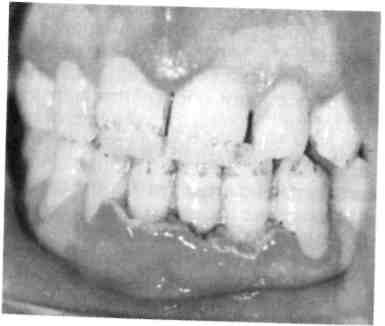

Гипертрофический гингивит пред­ставляет собой чаще всего хрони­ческий процесс и характеризуется пролиферацией десны на различных участках. Часто отмечается гипер­трофия передних отделов верхней и нижней челюстей (рис. 8.5).

Существенную роль в развитии такого гингивита играют гормо­нальные сдвиги (пре- и пубертат­ный периоды развития ребенка, во время беременности), дефицит ви­тамина С. Кроме того, гипертрофи­ческий гингивит нередко развива­ется при лечении детей с эпилеп­сией некоторыми препаратами (ди-фенин, гидантоин), реже при бо­лезнях крови (лейкемические рети-кулезы). Наиболее частой местной причиной развития такой патоло­гии является скученное положение зубов в переднем отделе верхней и/или нижней челюсти. Очаговый гипертрофический гингивит разви­вается под действием механической травмы (кламмер ортодонтического аппарата, нависающие края пломб, кариозный процесс придесневой локализации).

Течение гингивита хроническое, сопровождается деформацией рель­ефа десны, увеличением межзубных сосочков и десневого края. Разли­чают 3 формы заболевания: фиб­розную, гранулирующую (отечную) и смешанную.

В большинстве случаев преобла­дает продуктивный фиброзный про­цесс, при котором десневой край слабо кровоточит или не кровото­чит, больных беспокоит лишь нео­бычный вид десны. При гранулиру­ющей (отечной) форме десна темно-красного цвета, отличается значи-

Рис. 8.6. Гипертрофический гингивит после приема дифенина.

тельной пастозностью и кровоточи­востью, иногда отмечается боль при еде. При гранулирующей форме ги­пертрофического гингивита у де­тей, помимо разрастания десневых сосочков, определяется ее цианоз. Наиболее часто эти изменения на­блюдаются во фронтальном участ­ке, реже в области других зубов. При смешанной форме имеются признаки первых двух форм. При гипертрофическом гингивите, вы­званном приемом лекарственных средств, разрастание десны опреде­ляется не только с вестибулярной, но и с оральной поверхности (рис. 8.6).